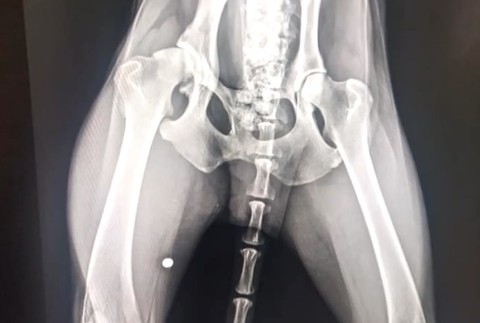

SPIŠSKÁ NOVÁ VES / Vyhladovaný na smrť, s brokom v tele a s vážne poranenou panvou. V takomto stave prijali týraného psíka pracovníci Slobody zvierat. Páchateľovi hrozí dvojročný pobyt za mrežami.

Psík sa stal terčom ľudskej krutosti. Okrem toho, že sa po ňom strieľalo, žil dlhodobo bez vody a jedla. Od veľkého hladu mal dokonca plný žalúdok nestrávených kostí. Jeho zdravotný stav bol doslova kritický.

Problémy zúboženému psíkovi navyše spôsoboval aj starší brok, ktorý mu uviazol v tele, keď po ňom strieľali. "Nevieme na základe čoho sa stal Odin terčom takejto ľudskej zloby. Bol mu nájdený brok v pravej zadnej končatine," dodala Devínska.